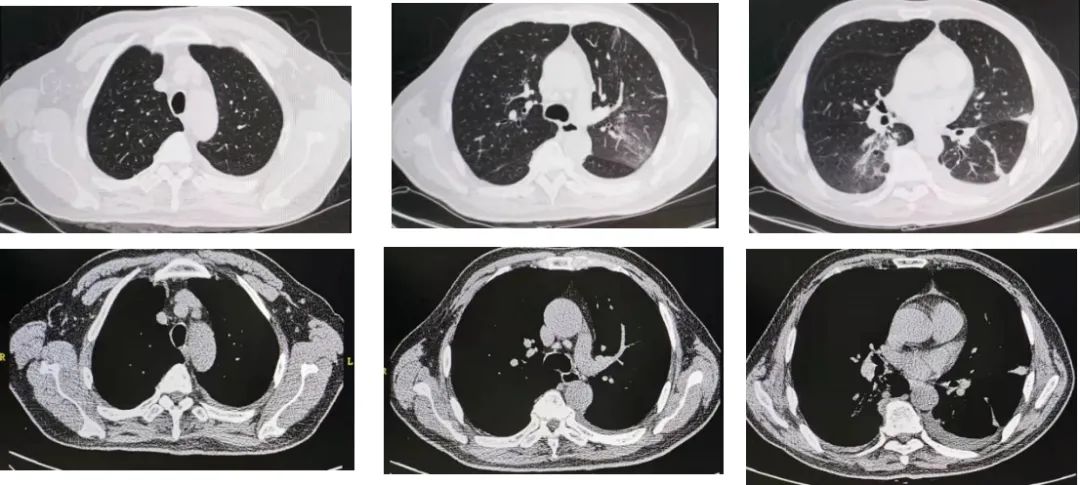

多西环素治疗2周后,患者未再出现发热症状,无头晕、乏力、呕吐等症状,一般情况良好。为了解肺部炎症吸收情况,我们复查了胸部CT(图11、图12):

图11:7月6日胸部CT。

图12:7月19日胸部CT,多西环素治疗后随访,肺炎较前明显吸收。